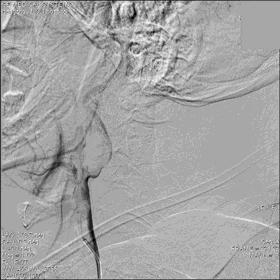

▼21:27穿刺成功,TOT 297min。左侧颈总动脉末端、颈内动脉起始部及颈外动脉起始部长条状血栓形成,随血流晃动,同侧大脑中动脉、大脑前动脉显影良好。

▼选用NAV 6 7.2 mm远端保护装置置于左侧颈内动脉C1段末端,将8F Gulding先后置于颈总动脉及颈内动脉开口部,50 ml注射器反复抽吸,抽出大量血栓。

▼颈总动脉及颈内动脉血栓抽吸完全,远端血流较前好转,TICI 3级。